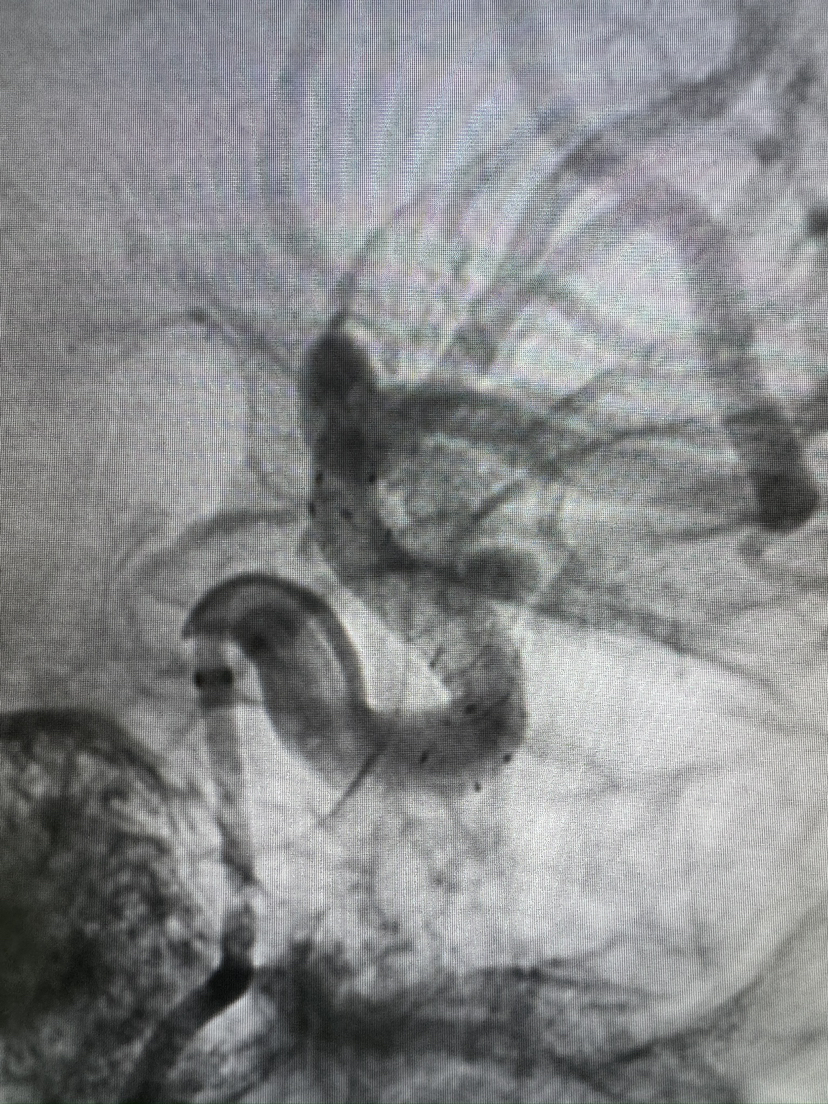

FRED血流导向密网支架栓塞眼动脉动脉瘤

#FRED®21 & FRED®27 血流导向密网支架

密网支架

动脉瘤

眼动脉